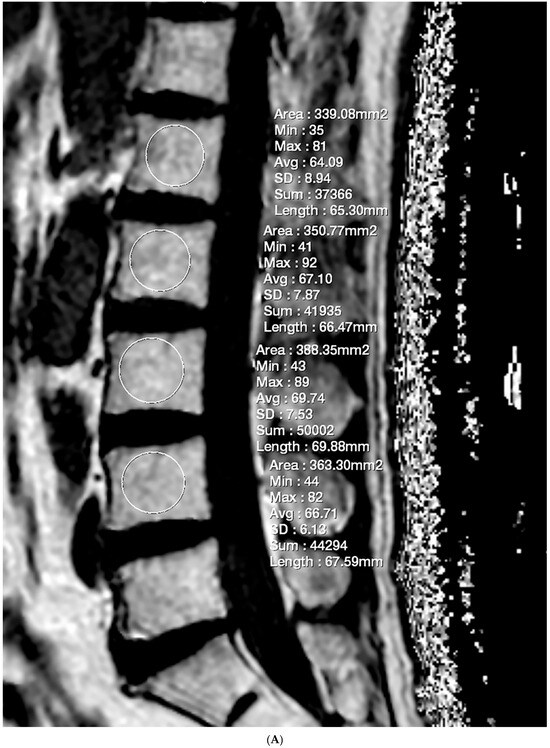

The FF measurement was independently performed by two radiologists who were unaware of the clinical information. Firstly, the FF measurements in GRE-based CSE-MRI were conducted using the INFINITT picture archiving and communication system. Elliptical regions of interest (ROIs) were drawn on the FF map, excluding the posterior venous complex and cortical bone, to encompass cancellous bone as much as possible (Figure 1). ROIs were delineated to the mid-sagittal image. In cases where obtaining information from the central image was challenging, ROIs were drawn on parasagittal images. Measurements were conducted on the L1–L4 bodies, and, in cases where abnormalities invaded all sagittal slices, this level was excluded from the measurements. The median values of the measurements were utilized as representative values (FFGRE). Next, the FF measurement in SE-based CSE-MRI was determined using diffusion analysis software (EXPRESS version 1.0, Philips Healthcare, Seoul, Republic of Korea). This program generates a fat fraction map by simply dividing the signal from the fat-only image by the sum of the signals from the water-only and fat-only images. After creating the FF map using mDixon-XD images, using the same criteria and methodology as in GRE-based CSE-MRI measurements, FF values were obtained from L1–L4 bodies (Figure 1), and the median was used as the representative value (FFSE).

Figure 1.

Lumbar spine MRI of a 59-year-old male. (A) Fat fraction (FF) measurement on gradient-echo (GRE)-based chemical-shift-encoded magnetic resonance imaging (CSE-MRI). The FFGRE in this patient was 66.91%, representing the median value of the L1–L4 vertebral bodies. (B) FF measurement on spin-echo (SE)-based CSE-MRI. The FFSE was 85.84%. The numbers in the figure indicate the ROI numbering in the EXPRESS program. (C) Measurement of the vertebral bone quality (VBQ) score was calculated by dividing the median value of T1-weighted signal of L1–L4 vertebral bodies by the cerebrospinal fluid (CSF) signal at the L3 level. The VBQ score for this patient was 2.63. (D,E) FF color maps were created through GRE- and SE-based CSE-MRI.